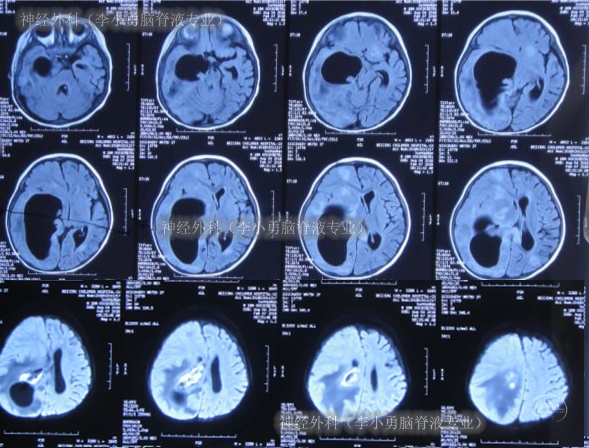

2018年1月23日(入院3天)接受了腰穿化验脑脊液提示细胞数增高,考虑是“化脓性脑膜炎”,2018年1月25日(入院后5天),查头MRI增强示脑内多发异常信号,考虑脑脓肿形成(图-1、图-2)。

图-1:2018年1月25日头部核磁增强

图-2:2018年1月25日头部核磁增强